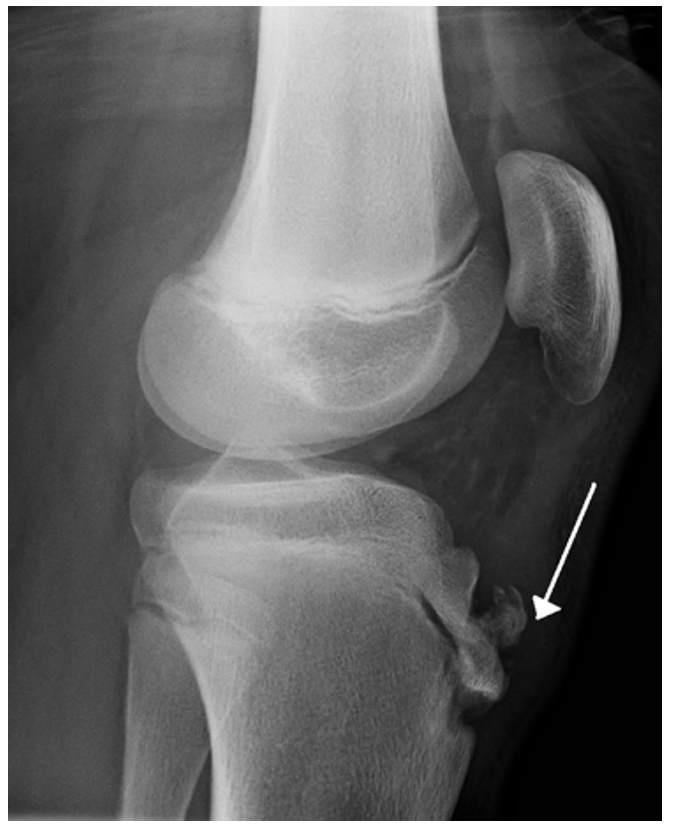

Patellar Dislocation

This refers to movement of the patella out of the patella groove

– It usually occurs when the knee is straight and then the lower leg is bent outwards when twisting, usually whilst playing sports like football.

– It is more likely to sublax laterally as the pull of vastus lateralis is stronger than that of vastus medialis.

– If the dislocation is partial, this is referred to a subluxation of the patella. This is more common than dislocation but just as disabling

– Visible subluxation of the patella laterally

Image 1: James Heilman, MD, CC BY-SA 3.0 <https://creativecommons.org/licenses/by-sa/3.0>, via Wikimedia Commons